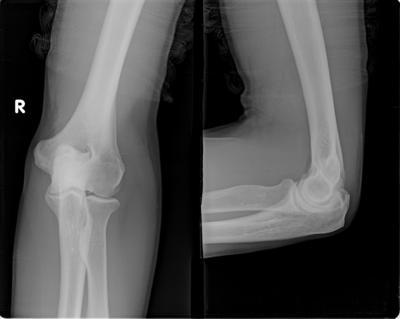

外周血白细胞计数升高,高达11×109/升(即11000/立方毫米),中性粒细胞比例也明显上升,高达85%,出现核左移现象。血沉和C-反应蛋白升高,血沉达87毫米/小时,C-反应蛋白在42毫克/升。RF(-)(类风湿因子)和ANA(抗核抗体)均为阴性。X线片显示膝关节软组织受损。

(图:患者肘关节疼痛,关节软组织受损)